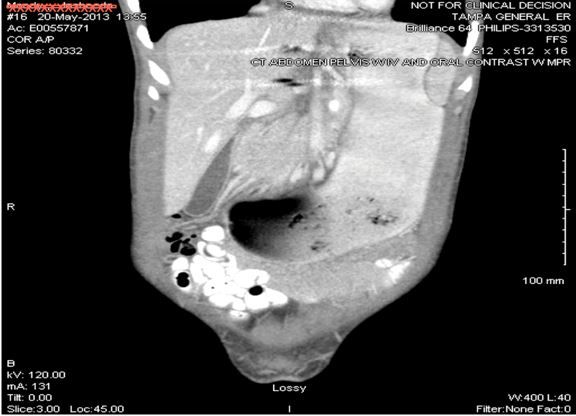

Figure 1. CT scan of abdomen, pelvis with contrast showing gastric obstruction.

On physical examination, the patient was thin and ill-appearing. Her abdomen was tender to palpation in all 4 quadrants with voluntary guarding and no rebound tenderness. Results of her laboratory work were significant only for a stable normocytic anemia. Abdominal CT showed marked distention of the stomach, consistent with gastric outlet obstruction (Figure 1; click to enlarge). Orders were made for the patient to receive nothing by mouth and a nasogastric tube was placed for gastric decompression.